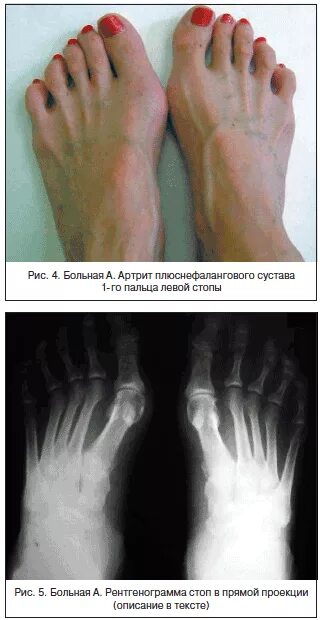

Артроз плюснефалангового сустава стопы